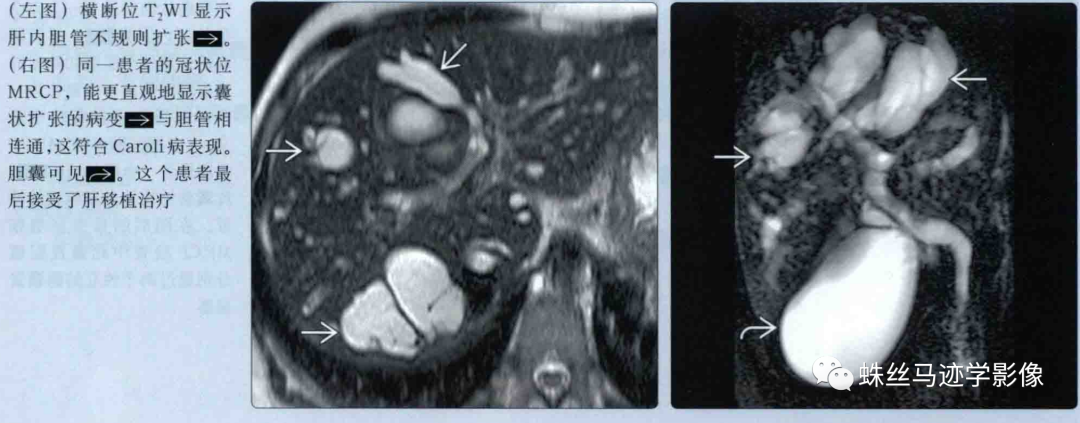

肝内胆管错构瘤和先天性肝内胆管囊状扩张症(Caroli病)-3